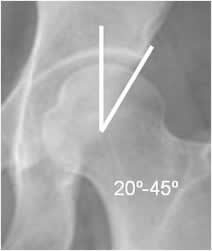

Permite determinar el cubrimiento de la cabeza femoral, por la cavidad acetabular. Está disminuido en casos de displasia y aumentado, en el pinzamiento tipo pincer. (16). Se traza con una línea vertical que se origina del centro de la cabeza femoral y su intersección, con otra que pasa por el borde externo del acetábulo. Su valor normal esta entre 20º y 45º. (17). (Fig 57 y 58).

Fig 57. Angulo de cubrimiento lateral normal.